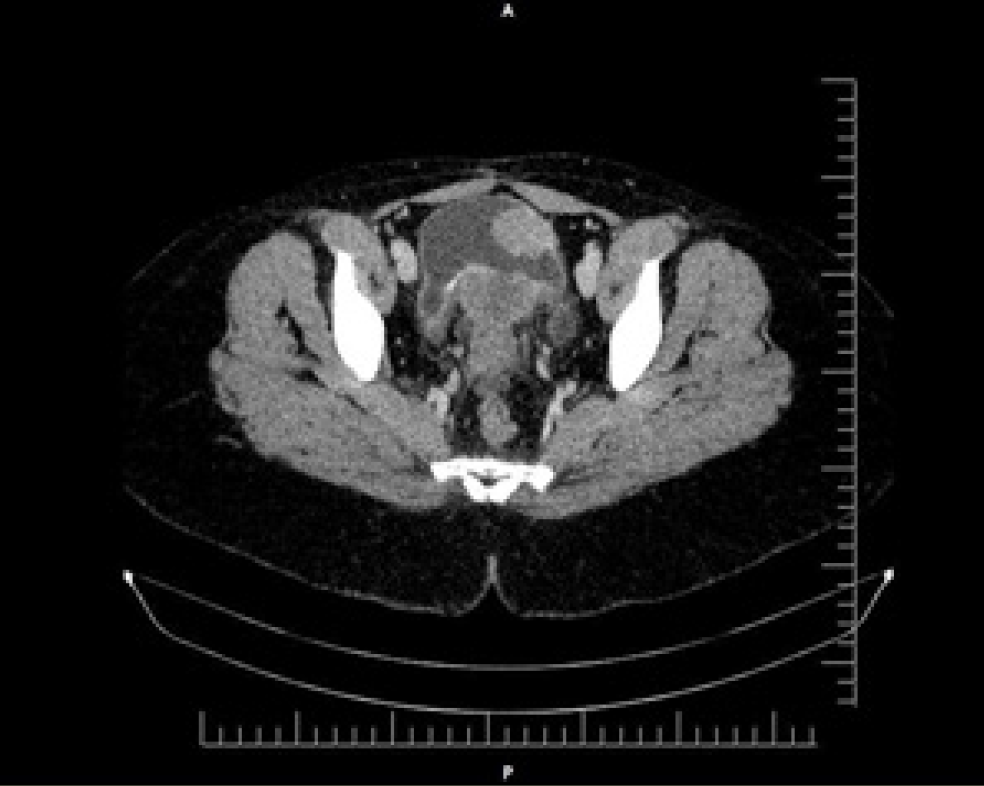

Case Presentation:  A 13-year-old girl presented with left loin pain, turbid yellow urine, and upper limb pain for over a month. Multiple evaluations, including laboratory and ultrasonographic investigations, were conducted. Ultrasound findings revealed severe enlargement of both kidneys, with the left kidney being larger than the right. A computerized tomography (CT) scan showed severe bilateral hydronephrosis and hydroureter, likely due to vesicoureteral junction obstruction. A left nephrectomy was performed; however, the patient continued to experience dysuria. During cystoscopy, a tumor was identified on the left posterolateral wall of the bladder. Surgical exploration revealed adhesion of the tumor to the uterus, bladder neck, and cervix. A cystectomy was recommended, during which part of the right ureter was removed, and the remaining portion was anastomosed to the sigmoid colon. Histopathological examination of the tissue samples revealed invasive squamous cell carcinoma (Grade 1) involving the cervix and vaginal wall. Additionally, multiple active and calcified Schistosoma haematobium eggs were observed. The patient was referred to the oncology unit for radio-chemotherapy, where she continues to receive treatment.